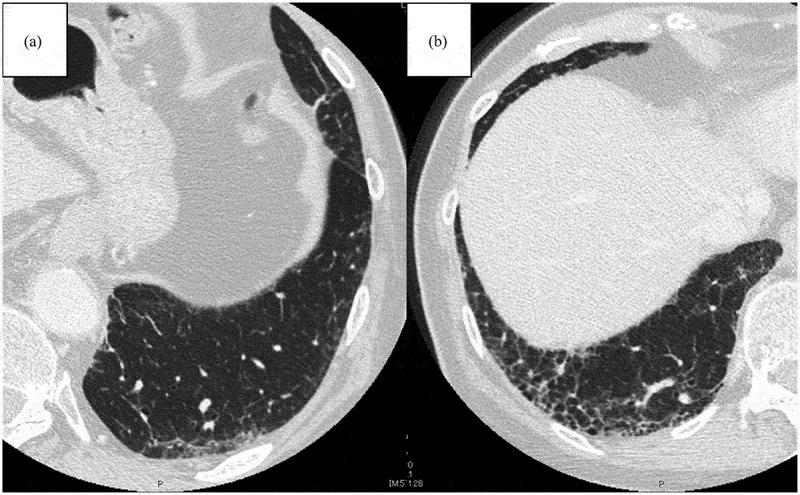

Immunotherapy has revolutionized the treatment landscape of non-small cell lung cancer (NSCLC), significantly improving survival outcomes and offering renewed hope to patients. However, the presence of interstitial lung abnormalities (ILAs) in patients with NSCLC presents unique challenges, especially due to the elevated risk of immune checkpoint inhibitor (ICI)-related pneumonitis, which can result in treatment interruptions and adversely affect prognosis. ILAs, often detected incidentally on computed tomography imaging, are associated with an increased risk of progression to interstitial lung disease and have been identified as a potential predictor of poor clinical outcomes in patients with NSCLC receiving immunotherapy. This review offers an overview of the current understanding of the interaction between ILAs and ICI therapy, discussing prevalence, radiological features, risk stratification, and management strategies. Additionally, it highlights the need for prospective, multicenter studies to establish optimal treatment modalities for patients with NSCLC having ILAs, to ensure safer and more effective immunotherapy.

免疫疗法彻底改变了非小细胞肺癌(NSCLC)的治疗格局,显著改善了生存结果,并为患者带来了新的希望。然而,NSCLC患者中存在的间质性肺异常(ILA)带来了独特的挑战,尤其是由于免疫检查点抑制剂(ICI)相关肺炎的风险升高,这可能导致治疗中断并对预后产生不利影响。ILA通常在计算机断层扫描成像中偶然发现,与进展为间质性肺病的风险增加相关,并已被确定为接受免疫疗法的NSCLC患者临床预后不良的潜在预测指标。本综述概述了目前对ILA与ICI治疗之间相互作用的理解,讨论了患病率、放射学特征、风险分层和管理策略。此外,它强调了开展前瞻性、多中心研究的必要性,以便为患有ILA的NSCLC患者建立最佳治疗模式,确保免疫疗法更安全、更有效。